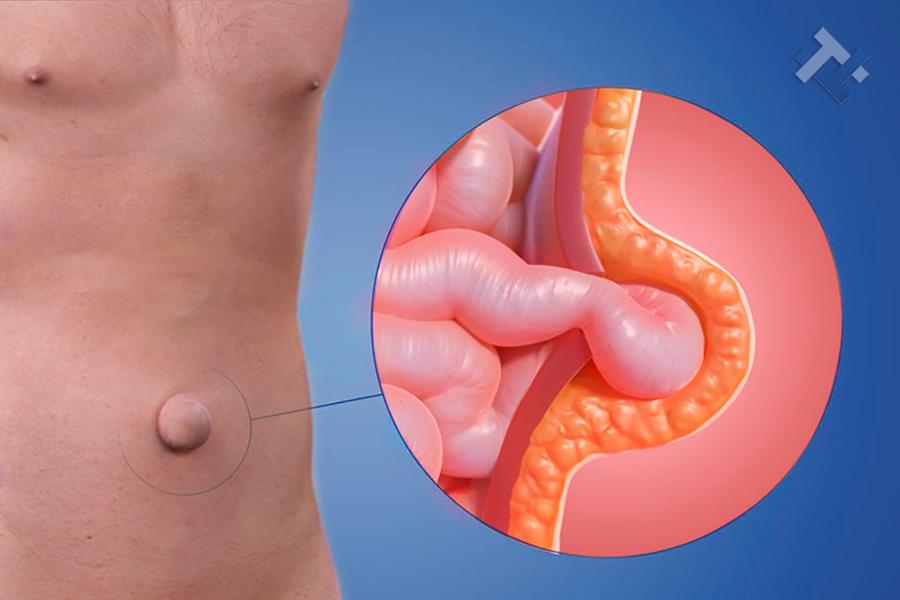

Κήλες - Κοιλιοκήλες:

Κήλες - Κοιλιοκήλες:

Ο Γενικός Χειρουργός Λιάγκος Γεώργιος MD PhD εκτελεί τις επεμβάσεις Λαπαροσκοπικά, Ενδοσκοπικά, Ανοιχτά Ελάχιστα Επεμβατικά και με Laser. Η θεραπεία εξατομικεύεται σε κάθε ασθενή ανάλογα με τις ανάγκες του. Αναλαμβάνει περιπτώσεις όπως κήλες και κοιλιοκήλες (αντιμετώπιση βουβωνοκήλης, αντιμετώπιση ομφαλοκήλης, θεραπεία επιγαστρικής κήλης, κήλη των αθλητών (Σύνδρομο κοιλιακών προσαγωγών), αντιμετώπιση μετεγχειρητικής κήλης, θεραπεία Μηροκήλης), πέτρες στη χοληδόχο κύστη, λαπαροσκοπική χολοκυστεκτομή, αντιμετώπιση Κύστη Κόκκυγος με λέιζερ (laser), παθήσεις πρωκτού, χειρουργική laser σύγχρονων κυκλικών ινών (αιμορροΐδες αντιμετώπιση, θεραπεία αιμορροϊδων με laser (LHP), αφαίρεση αιμορροΐδων με υπερήχους (HALL-RAR), χωρίς Χειρουργείο με ελαστικούς δακτυλίους (Τεχνική BARON-RBL), θεραπεία ραγάδας πρωκτού (Ραγάδα δακτυλίου), θεραπεία περιεδρικού συριγγίου, θεραπεία περιεδρικού αποστήματος, κονδυλώματα πρωκτού Θεραπεία, δερματικό ράκος (Skin tag) εκτομή, αντιμετώπιση Kνησμού, καρκίνος πρωκτού θεραπεία), παθήσεις Δέρματος, χειρουργική με laser CO2, αφαίρεση μορφωμάτων δέρματος - βιοψίες, αφαίρεση ελιάς (Σπίλου), σμηγματογόνος κύστης θεραπεία, αφαίρεση λιπώματος, είσφρυση όνυχος χειρουργείο, καρκίνος δέρματος θεραπεία, οξεία σκωληκοειδίτιδα, παθήσεις Λεπτού και Παχέος Εντέρου, ειλεός λεπτού εντέρου, εκκολπωμάτωση (Εκκολπωματίτιδα) σιγμοειδούς, καρκίνος παχέος εντέου, κολοστομίες, port χημειοθεραπείας κ.α.

Ο Γενικός Χειρουργός Λιάγκος Γεώργιος MD PhD εκτελεί τις επεμβάσεις Λαπαροσκοπικά, Ενδοσκοπικά, Ανοιχτά Ελάχιστα Επεμβατικά και με Laser. Η θεραπεία εξατομικεύεται σε κάθε ασθενή ανάλογα με τις ανάγκες του. Αναλαμβάνει περιπτώσεις όπως κήλες και κοιλιοκήλες (αντιμετώπιση βουβωνοκήλης, αντιμετώπιση ομφαλοκήλης, θεραπεία επιγαστρικής κήλης, κήλη των αθλητών (Σύνδρομο κοιλιακών προσαγωγών), αντιμετώπιση μετεγχειρητικής κήλης, θεραπεία Μηροκήλης), πέτρες στη χοληδόχο κύστη, λαπαροσκοπική χολοκυστεκτομή, αντιμετώπιση Κύστη Κόκκυγος με λέιζερ (laser), παθήσεις πρωκτού, χειρουργική laser σύγχρονων κυκλικών ινών (αιμορροΐδες αντιμετώπιση, θεραπεία αιμορροϊδων με laser (LHP), αφαίρεση αιμορροΐδων με υπερήχους (HALL-RAR), χωρίς Χειρουργείο με ελαστικούς δακτυλίους (Τεχνική BARON-RBL), θεραπεία ραγάδας πρωκτού (Ραγάδα δακτυλίου), θεραπεία περιεδρικού συριγγίου, θεραπεία περιεδρικού αποστήματος, κονδυλώματα πρωκτού Θεραπεία, δερματικό ράκος (Skin tag) εκτομή, αντιμετώπιση Kνησμού, καρκίνος πρωκτού θεραπεία), παθήσεις Δέρματος, χειρουργική με laser CO2, αφαίρεση μορφωμάτων δέρματος - βιοψίες, αφαίρεση ελιάς (Σπίλου), σμηγματογόνος κύστης θεραπεία, αφαίρεση λιπώματος, είσφρυση όνυχος χειρουργείο, καρκίνος δέρματος θεραπεία, οξεία σκωληκοειδίτιδα, παθήσεις Λεπτού και Παχέος Εντέρου, ειλεός λεπτού εντέρου, εκκολπωμάτωση (Εκκολπωματίτιδα) σιγμοειδούς, καρκίνος παχέος εντέου, κολοστομίες, port χημειοθεραπείας κ.α.